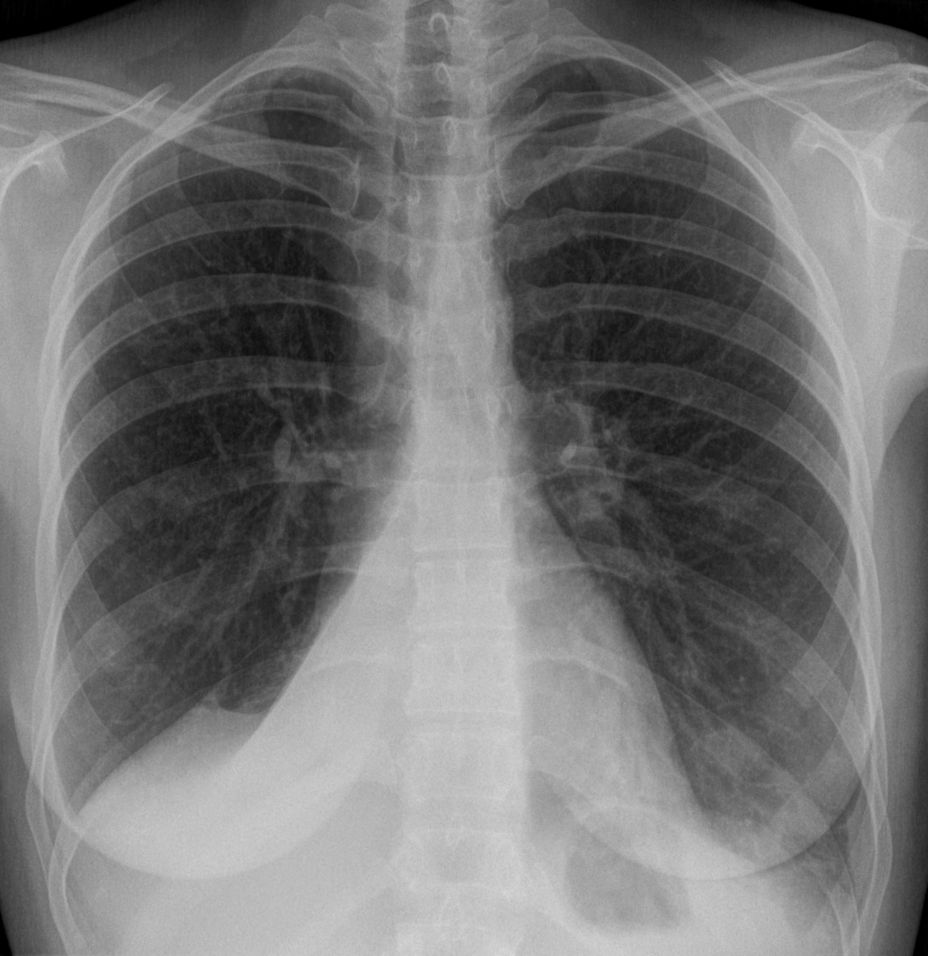

임상적으로 유의미한 무기폐는 일반적으로 흉부 엑스레이에서 관찰 가능하며, 폐의 불투명화 및/또는 폐 용적 감소와 같은 소견을 보일 수 있다. 수술 후 무기폐는 양쪽 기저부에서 나타나는 양상을 보인다. 무기폐의 원인이 임상적으로 명확하지 않은 경우 흉부 CT 또는 기관지 내시경이 필요할 수 있다.[10] 무기폐의 직접적인 징후로는 엽간 열구 및 흉강 내 이동성 구조의 변위, 영향을 받지 않은 동측 폐엽 또는 반대쪽 폐의 과도한 팽창, 그리고 허탈된 폐엽의 불투명화가 있다.[10] 흉부 엑스레이에서 임상적으로 유의미한 소견 외에도, 환자는 횡격막의 상승, 기관, 심장 및 종격동의 이동, 폐문의 변위 및 육아종의 이동과 같은 간접적인 징후와 증상을 나타낼 수 있다.[10]

• 흉부 엑스레이 사진

흉부 엑스레이에서 보이는 오른쪽 아래 엽의 무기폐